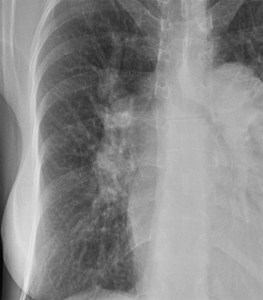

SIGNO DEL TUMOR FANTASMA O TUMOR EVANESCENTE

Signo que describe al derrame pleural atrapado en la cisura menor, especialmente en pacientes con insuficiencia cardiaca. El derrame loculado en la proyección posteroanterior se ve como una lesión nodular o masa que simula un tumor sólido (imagen superior). Sin embargo, la evolución rápida hacia la desaparición de esta lesión sugiere que se trata de derrame.

Vemos en las imágenes un tumor fantasma que desaparece en el control realizado cinco días más tarde.

En la primera imagen, la presencia de derrame pleural asociado y el engrosamiento del resto de la cisura menor, visible como una línea superpuesta al tumor fantasma, sugieren el diagnóstico.